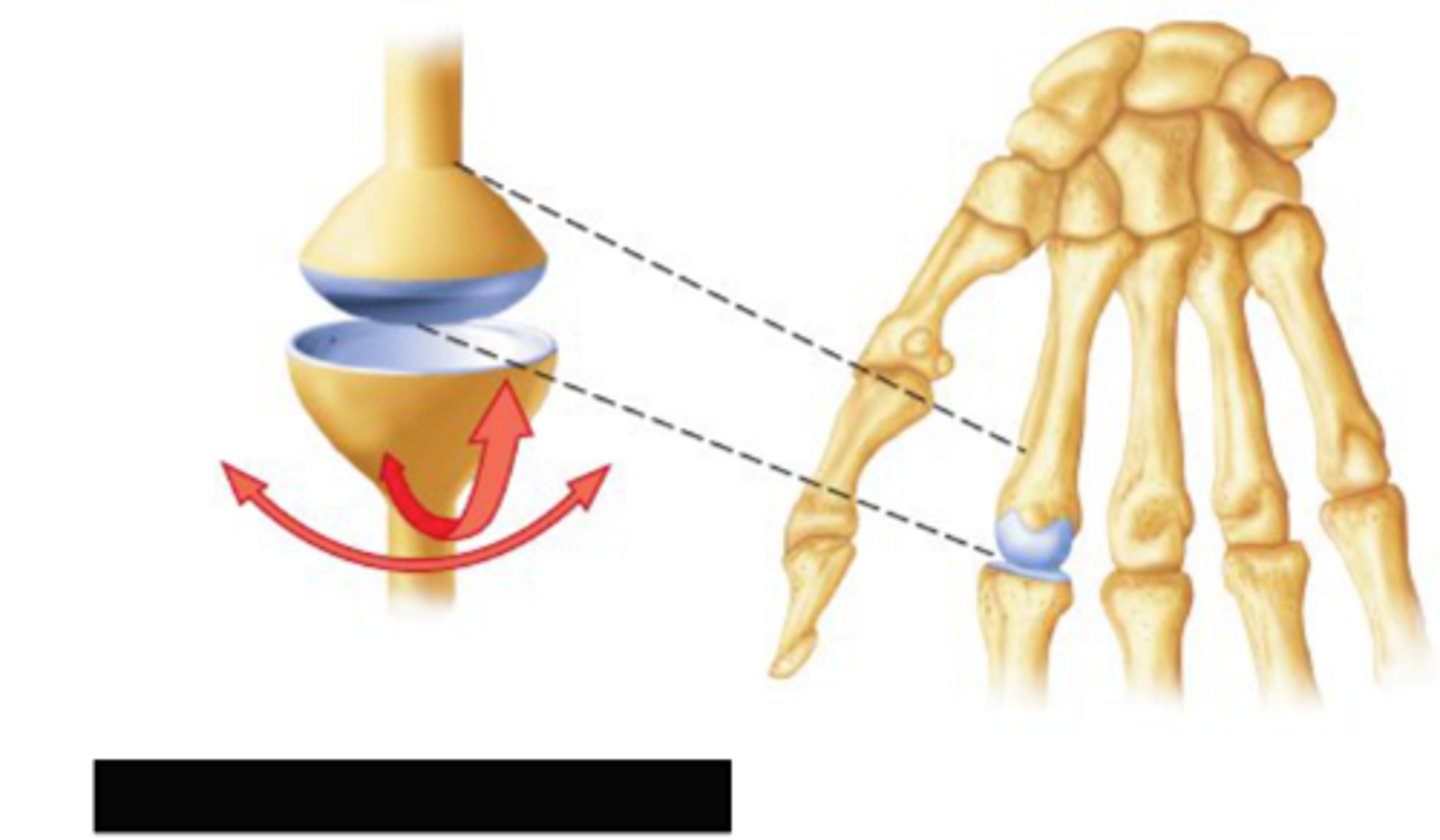

Condylar synovial joint

allow movement around two axes that are at right angles to each other

-permits flexion, extension, abduction, adduction, and circumduction

ex: wrist joint